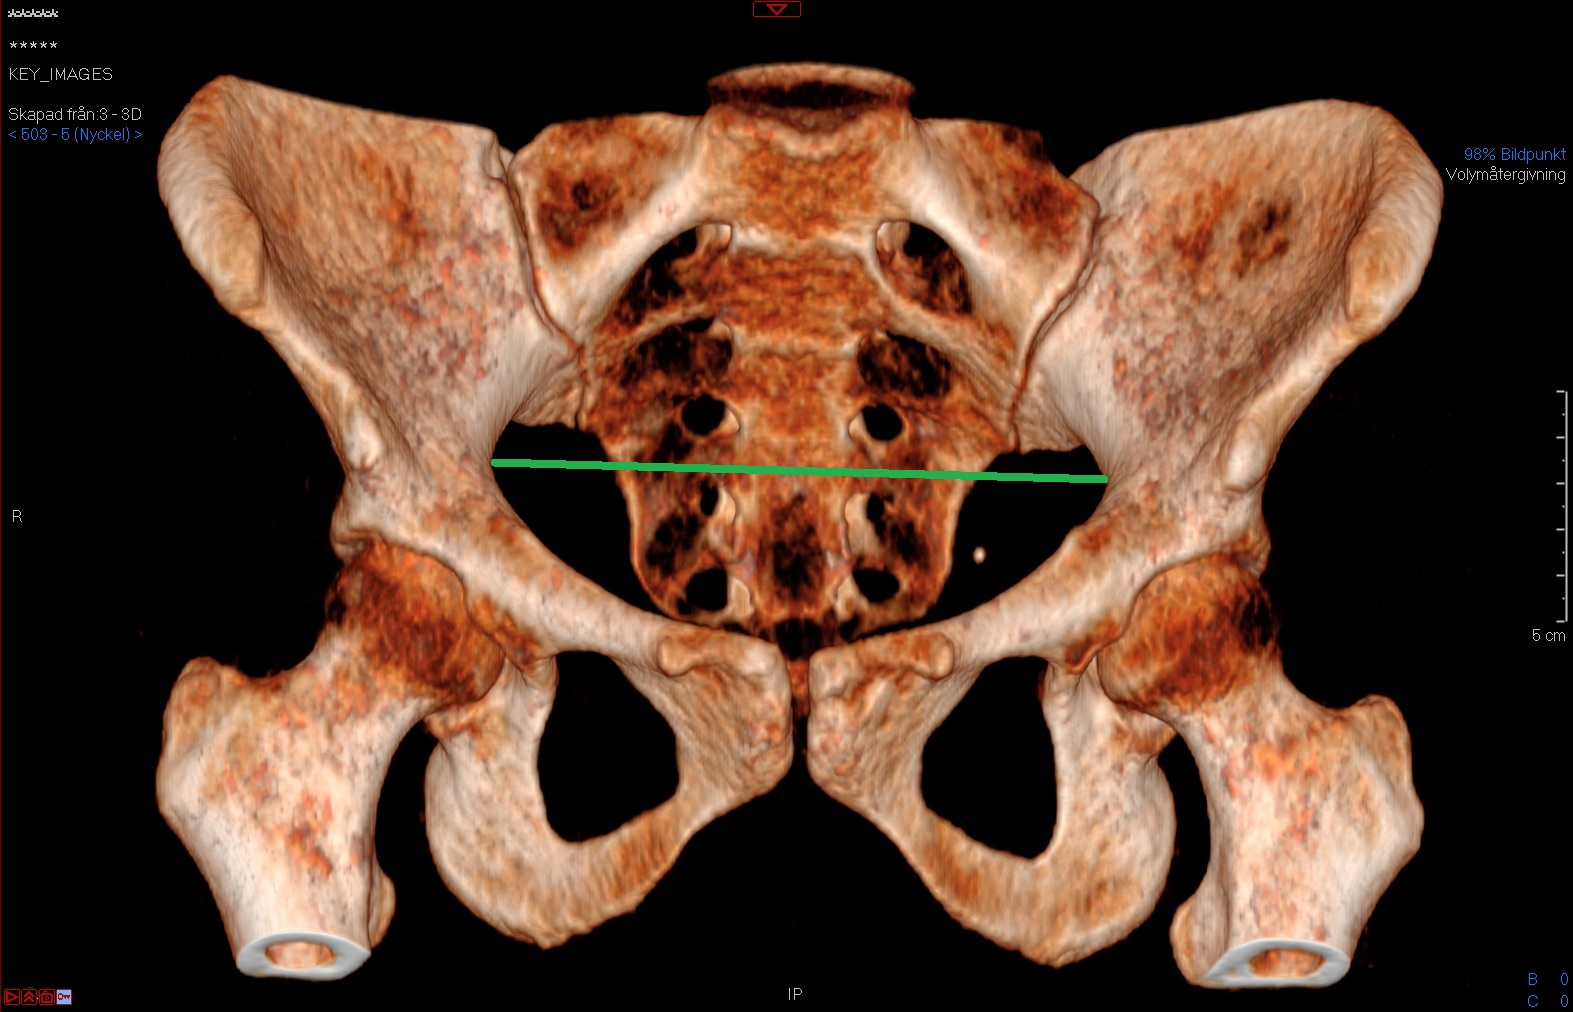

Tunna snitt-serien i 3D-modulen. Vinkla så att bäckenet blir rakt och att symfysen överlappar coccyx och spara en nyckelbild. Både diameter transversa och intertuberavståndet mäts i den sparade nyckelbilden (INTE i 3D-modulen).